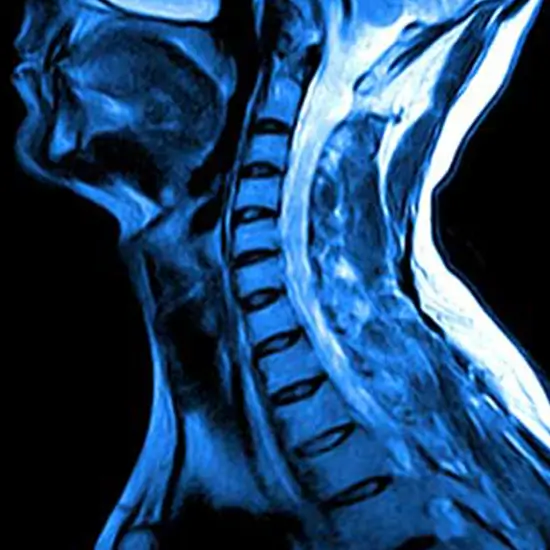

An MRI Screening of the CX-Dorsal Spine is also known as MRI Screening of the cervical dorsal spine or MRI screening Cervico- Dorsal Spine. It is an imaging procedure that uses powerful magnetic energy to create pictures of the spine that goes up through the neck area, mid-back, and upper back.  The scan creates detailed 3D images to identify the disorders in the muscles, soft tissues, nerves, and disks of the vertebral section.

This procedure is performed to detect and diagnose problems such as bone injury and fractures, genetic defects in the vertebral column, tumors or cysts in the region, etc.